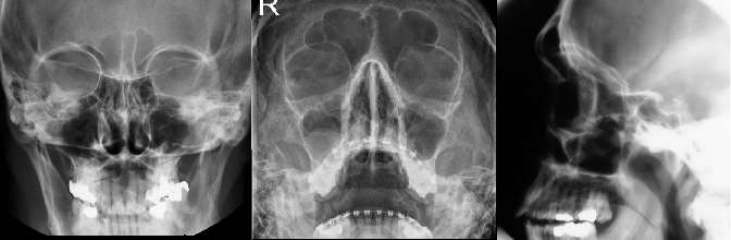

Exame convencional – 3 incidências:

- Caldwell ou frontonaso (PA): seios frontais, maxilares e etmoidais

- Waters (occiptomentoniana ou mentonaso): seios maxilares e frontais

- Lateral: parede anterior e posterior dos seios frontais e maxilares, visibilização moderada do seio

esfenoidal e dos seios etmoidais